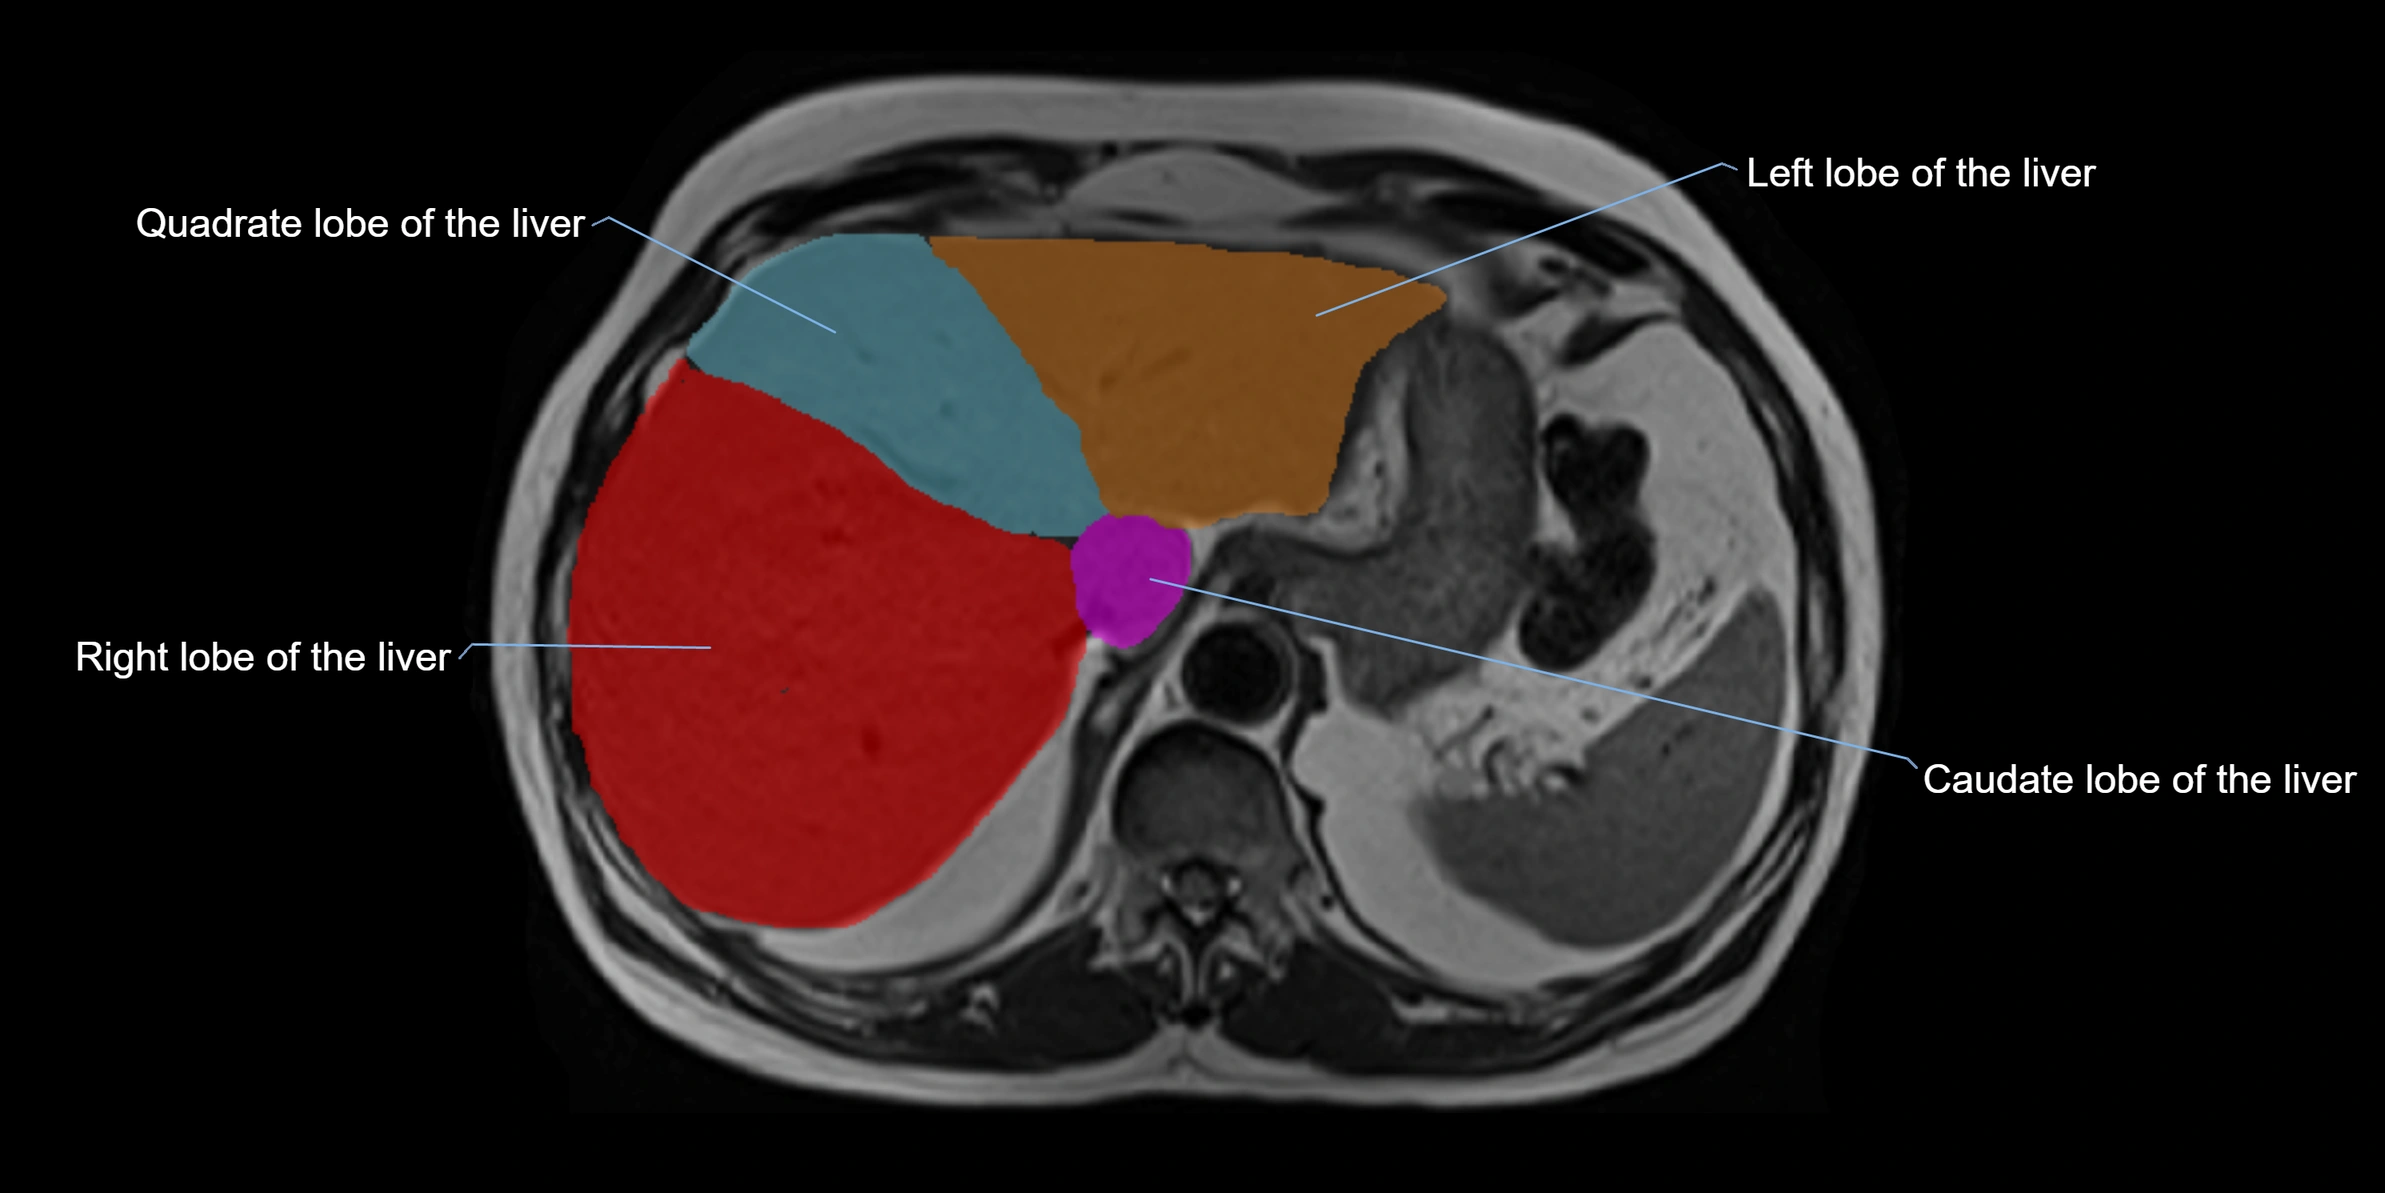

The caudate lobe of the liver is a distinct anatomical subdivision of the liver, designated as segment I in Couinaud’s classification. It lies on the posterior surface of the liver, between the fissure for the ligamentum venosum (left boundary) and the groove for the inferior vena cava (IVC) (right boundary). Superiorly, it is related to the posterior liver surface, and inferiorly it is separated from the left lobe by the porta hepatis.

The caudate lobe is unique because it receives dual portal venous and arterial inflow from both the right and left portal veins and hepatic arteries. It also has independent venous drainage directly into the IVC via multiple small hepatic veins, unlike other lobes that drain through the three main hepatic veins.

This anatomical autonomy makes the caudate lobe especially significant in liver surgery, transplantation, and hepatic venous outflow obstruction syndromes (e.g., Budd–Chiari syndrome). Enlargement of the caudate lobe is a characteristic imaging feature in chronic liver disease and cirrhosis.